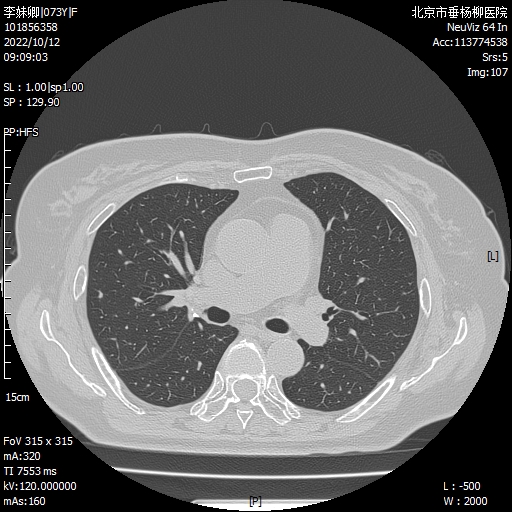

病例概要:患者女性,73岁,主因“发现右肺结节7月。”以“右肺结节,性质待查”入院,胸部CT:右肺可见多发磨玻璃微结节影,边界较清,大者直径约4mm。抗炎治疗无效,恶性不除外,行电视胸腔镜辅助下右肺上叶后段切除术,术中可见脏壁层胸膜光滑,叶裂分化完全,术顺,手术历时2小时,完整切除可疑结节病灶,术后病理回示,分别为:1.不典型腺瘤样增生(AAH);2.良性病变(肺泡上皮轻度反应性增生,伴炭末沉积及淋巴细胞聚集)。术后患者恢复良好,术后2天拔出引流管,4天出院。